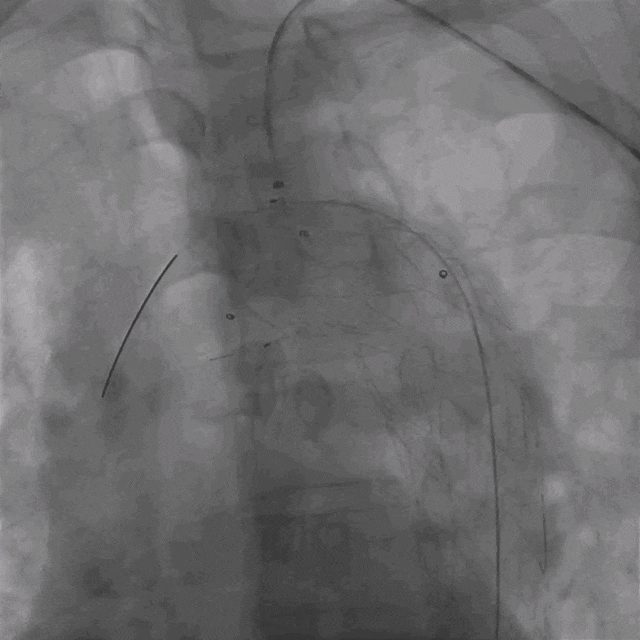

03. 左侧肱动脉采用0.035"泥鳅导丝硬头配合支撑导管顺利破膜,引入4mm球囊予以开窗处扩张。

泥鳅导丝怎么用曲乐丰教授团队:0.018"和0.035"普通泥鳅导丝行胸主动脉弓上分支原位开窗的病例分享_https://www.jmylbn.com_新闻资讯_第31张

调节支撑导管垂直于覆膜

泥鳅导丝怎么用曲乐丰教授团队:0.018"和0.035"普通泥鳅导丝行胸主动脉弓上分支原位开窗的病例分享_https://www.jmylbn.com_新闻资讯_第32张

泥鳅导丝硬头顺利破膜